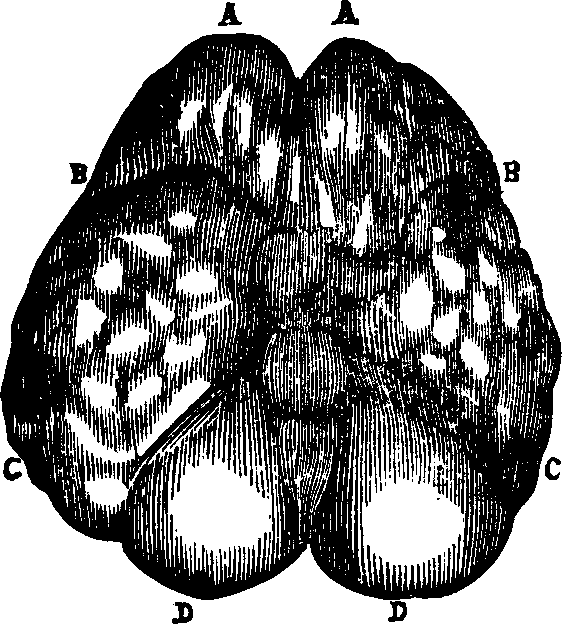

converted into a homogeneous fluid, which pervades every part of the body,

is the basis of every tissue, and which is termed the blood. This

varies in color and composition in different animals. In the polyp the

nutritive fluid is known as chyme, in many mollusks, as well as

articulates, it is called chyle, but in vertebrates, it is more

highly organized and is called blood. In all the higher animal types it is

of a red color, although redness is not one of its essential qualities.

Some tribes of animals possess true blood, which is not red; thus the blood

of the insect is colorless and transparent; that of the reptile yellowish;

in the fish the principle part is without color, but the blood of the bird